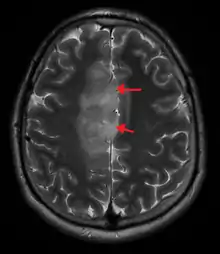

| A oligoastrocytoma on CT | |

An X-ray computed tomography (CT) or magnetic resonance imaging (MRI) scan is necessary to characterize the anatomy of this tumor as to size, location, and its heter/homogeneity. However, final diagnosis of this tumor, like most tumors, relies on histopathologic examination (biopsy examination).[3]